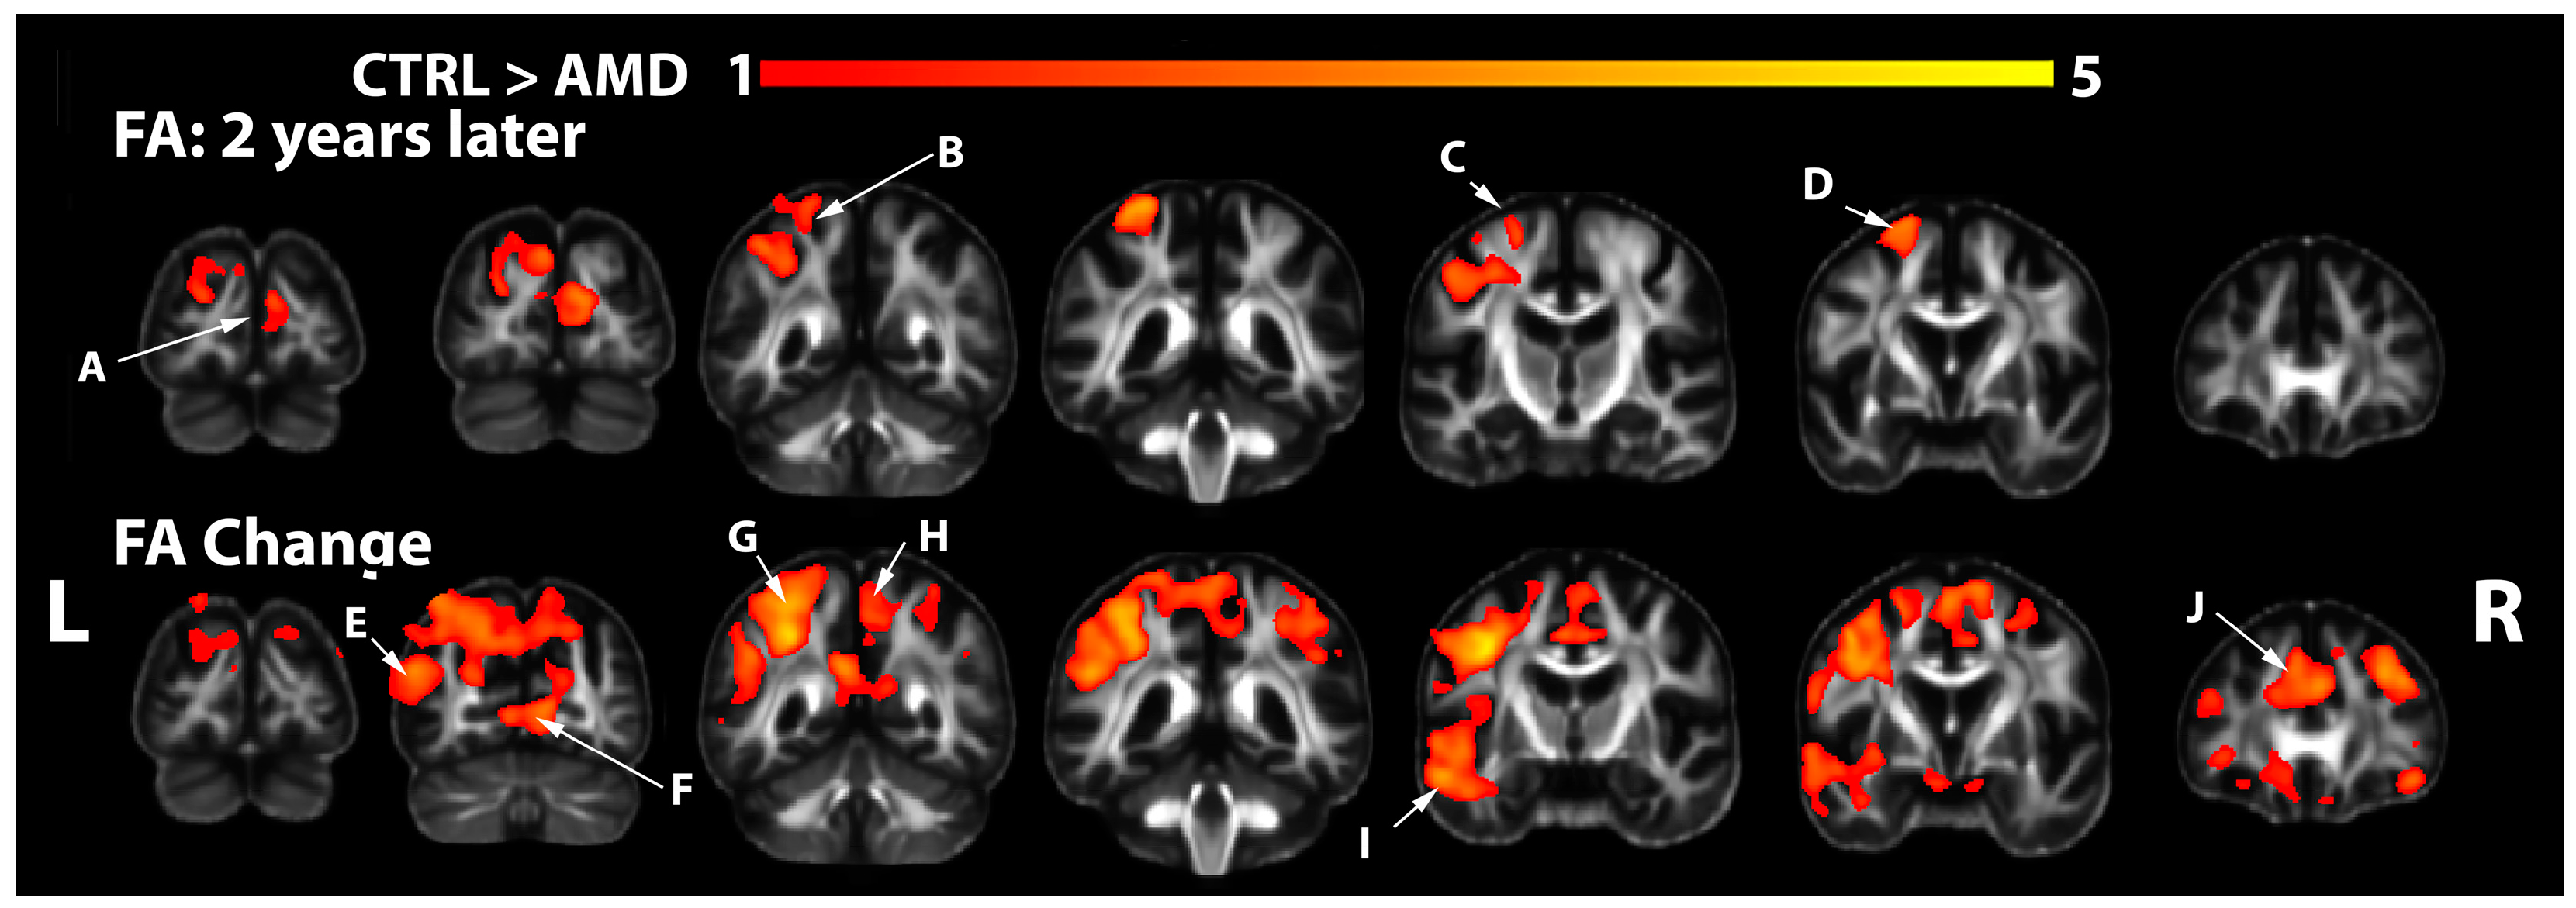

3.2. FA Changes in AMD Participants